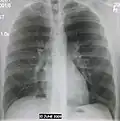

Normal AP CXR

Normal lateral CXR -

Left upper lobe pneumonia with a small pleural effusion.